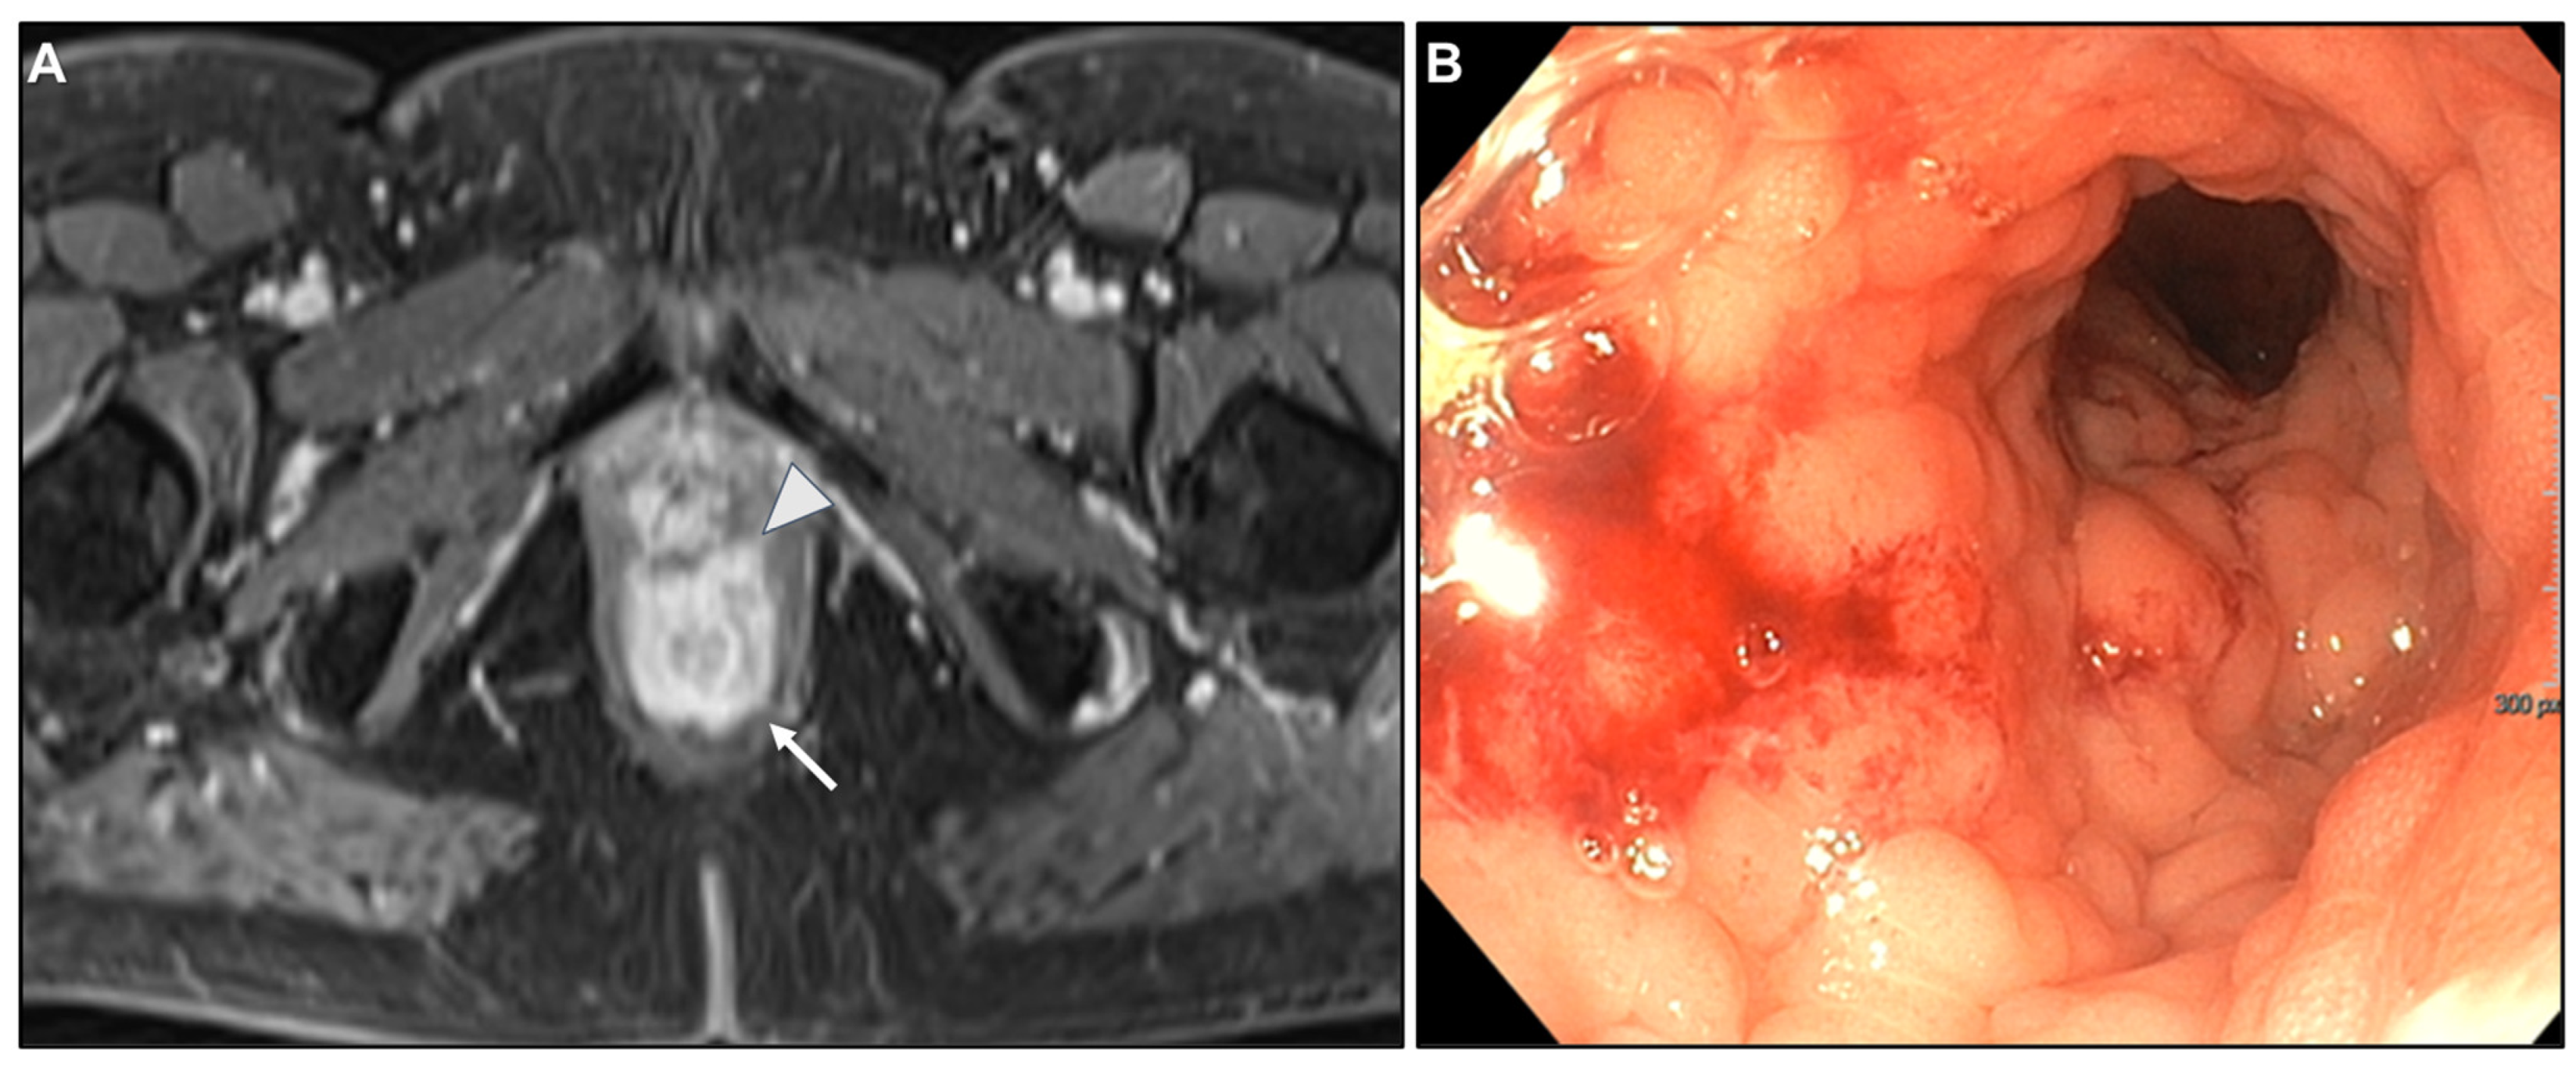

Presacral Fat Tissue and Rectovaginal Septum Infiltration and T2-Weighted Imaging (T2WI) Hypointense Extramural Tumour Component

- Lau, L.C.; Wee, B.; Wang, S.; Thian, Y.L. Metastatic breast cancer to the rectum: A case report with emphasis on MRI features. Medicine 2017, 96, e6739. [Google Scholar] [CrossRef] [PubMed]

- Rudralingam, V.; Dobson, M.J.; Pitt, M.; Stewart, D.J.; Hearn, A.; Susnerwala, S. MR imaging of linitis plastica of the rectum. AJR Am. J. Roentgenol. 2003, 181, 428–430. [Google Scholar] [CrossRef] [PubMed]

- Mazza, S.; Laurenza, C.; Elvo, B.; Tanzi, G.; Ungari, M.; Soro, S.; Verga, M.C.; Drago, A.; Grassia, R. Rectal linitis plastica as the first presentation of metastatic lobular breast cancer: An endoscopic ultrasound diagnosis. Clin. J. Gastroenterol. 2022, 15, 1072–1077. [Google Scholar] [CrossRef] [PubMed]